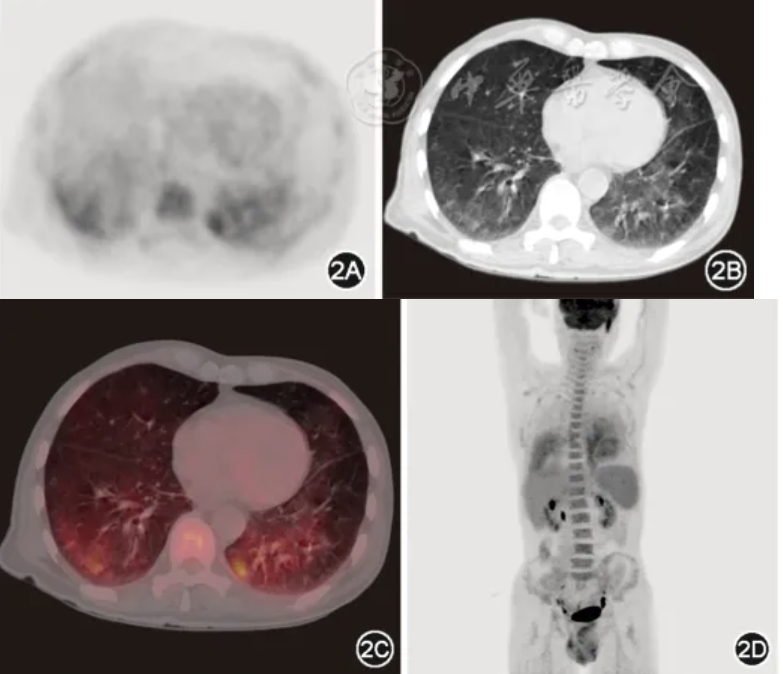

PET/CT:双肺广泛分布的磨玻璃密度影,代谢增高,最大标准化摄取值(SUVmax)为 5.5(图2)。

图2 患者2023年8月8日PET/CT检查,其中图2A为PET-CT胸部横断位图像,图2B为同机器的胸部CT图像,图2C为融合图像,图2D为全身最大密度冠状位投影图,可见双肺广泛分布的磨玻璃密度影,放射性摄取增高,SUVmax值为5.5,分布呈重力依赖性

本例患者为老年男性,临床主要表现为快速进展的呼吸困难,伴发热、消瘦等全身炎症状态。病初糖皮质激素治疗有效,但减量后病情反复,后期出现神经系统和血液系统受累。实验室检查提示血清LDH、IL-10显著升高,多次筛查外周血、下呼吸道病原学均无感染性疾病相关证据,虽存在ANCA低滴度阳性,但无咯血、血红蛋白明显下降等显微镜下多血管炎典型弥漫性肺泡出血表现;而影像学检查以肺内病变较为突出,胸部CT表现为双肺沿重力分布的弥漫性磨玻璃影(ground glass opacity,GGO),且PET/CT提示代谢性摄取增高,同时超声提示脾大。因此需高度警惕弥漫浸润的血液系统肿瘤,经积极寻找病理证据,最终通过TBLB小标本明确诊断。

IVLBCL患者肺受累主要表现为发热、咳嗽和劳力性呼吸困难等非特异性症状[10, 11]。实验室检查常见血清IL-10及LDH显著升高,其水平可能是IVLBCL早期诊断和疗效监测的有效生物标志物[12, 13, 14, 15]。由于大量淋巴瘤细胞聚集在毛细血管内,IVLBCL肺受累典型的胸部CT与其他肺淋巴瘤不同,常表现为双侧弥漫性GGO,其次也可表现为弥漫性分布的小结节影、实变影和小叶间隔增厚等[16, 17, 18],甚至可能无明显异常[19],而非实变和肿块。此外,18F-FDG PET-CT对肺IVLBCL的诊断具有较高提示意义[20, 21, 22],特别是在存在呼吸系统症状但胸部CT未见异常的患者中[21,23],主要表现为双肺均匀弥漫性的代谢摄取增高。